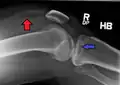

A tibial plateau fracture seen on X-ray